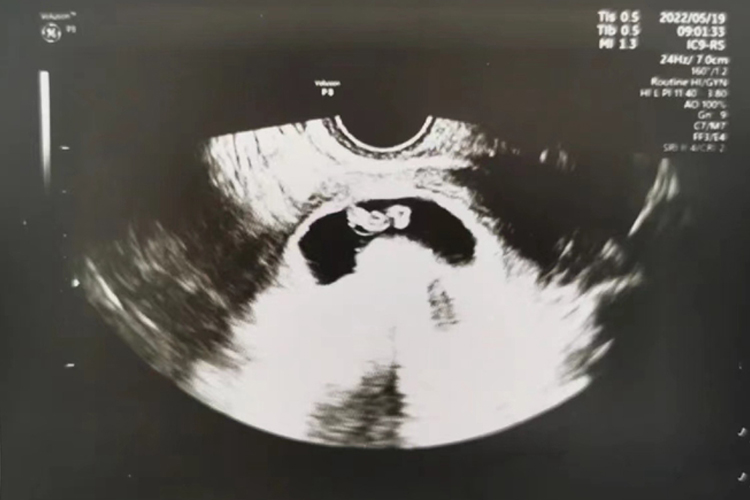

孕7周时胚胎整体形态像“9”一样,其面部器官明显,可看到四肢。此时孕妇可能伴随早孕反应,建议合理的休息与运动。

怀孕第7周时,胚胎仍然漂浮在羊膜囊中,身长约为1.2厘米,体重约1克,且头部增大明显,与身体显得有些不成比例。胚胎的面部器官比较明显,眼睛像一个明显的黑点,鼻孔大开着,耳朵有些凹陷。胚胎上伸出的幼芽将长成胳膊和腿,看上去已经明显。